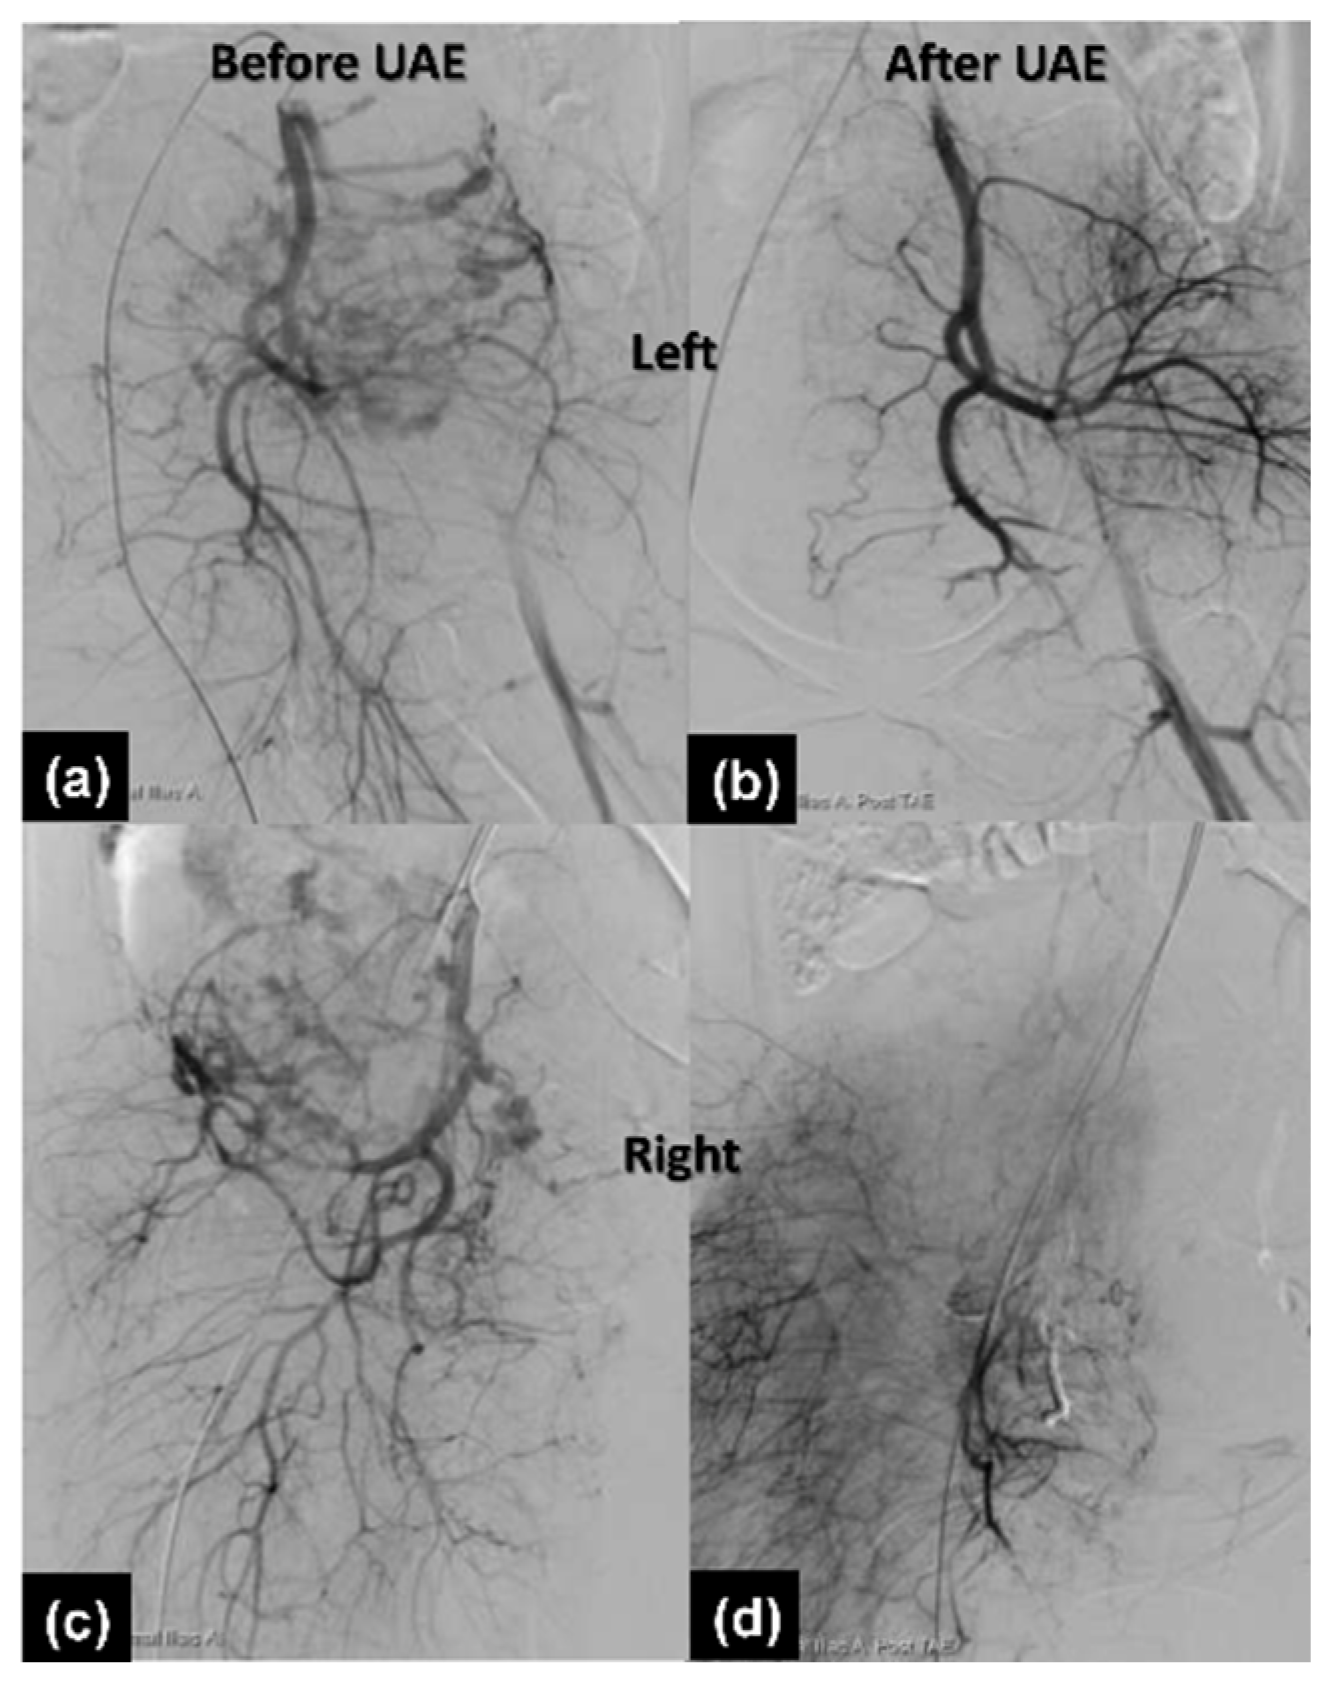

2.1.3. Therapeutic Intervention

2.1.4. Follow-Up and Outcomes